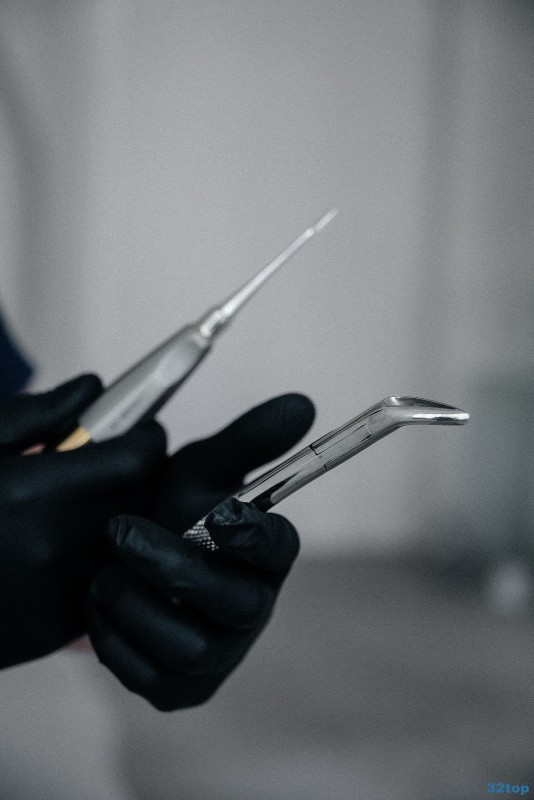

Примеры работ